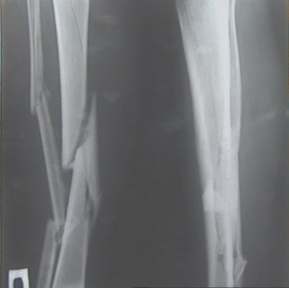

Уважаемые коллеги! На консультации больной предъявляет жалобы на хромоту (укорочение - 2см), боль в месте перелома при нагрузке (спортсмен).

Семь месяцев назад получил закрытый перелом, лечился консервативно в одной из больниц города. Как-бы кто лечил? Сам склоняюсь к LCP с костной пластикой.

Юрий Алексеевич, привет. А перелом то вроде сросся! -правда с варусом - угол можно посчитать у Вас по снимкам (в письме - суставов нет в прямой проекции). Я бы не спешил, с открытой хирургией тем более. Риски велики. Укорочение абсолютное тоже мизерно. А коррекцию оси сделал бы попозже малоинвазивным методом по Илизарову ГА.

У нас, наверно, была бы сделана чрескожная остеотомия малоберцовой кости, формирование и рассверливание канала большеберцовой, закрытая остеоклазия, и закрытое же штифтование. За счет устранения варуса дефицит длины уменьшится. Можно и подтянуть дистрактором одномоментно.